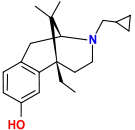

Benzomorphans

- 5,9 alpha-diethyl-2-hydroxybenzomorphan (5,9-DEHB)

- 8-Carboxamidocyclazocine (8-CAC)

- Alazocine

- Anazocine

- Bremazocine

- Butinazocine

- Carbazocine

- Cogazocine

- Cyclazocine

- Dezocine

- Eptazocine

- Etazocine

- Ethylketazocine

- Fedotozine

- Fluorophen

- Gemazocine

- Ibazocine

- Ketazocine

- Metazocine

- Moxazocine

- Pentazocine

- Phenazocine

- Quadazocine

- SKF-10047

Structures

| Benzomorphans | ||||

|---|---|---|---|---|

5,9 alpha-diethyl-2-hydroxybenzomorphan 5,9 alpha-diethyl-2-hydroxybenzomorphan (5,9-DEHB) |

8-Carboxamidocyclazocine 8-Carboxamidocyclazocine |

Alazocine Alazocine |

Anazocine Anazocine |

Bremazocine Bremazocine |

Butinazocine Butinazocine |

Carbazocine Carbazocine |

Cogazocine Cogazocine |

Cyclazocine Cyclazocine |

Dezocine Dezocine |

Eptazocine Eptazocine |

Etazocine Etazocine |

Ethylketocyclazocine Ethylketocyclazocine |

Fedotozine Fedotozine |

Fluorophen Fluorophen |

Gemazocine Gemazocine |

Ibazocine Ibazocine |

Ketazocine Ketazocine |

Metazocine Metazocine |

Moxazocine Moxazocine |

Pentazocine Pentazocine |

Phenazocine Phenazocine |

Quadazocine Quadazocine

|

Thiazocine Thiazocine |

Tonazocine Tonazocine |

Volazocine Volazocine |

Zenazocine Zenazocine |